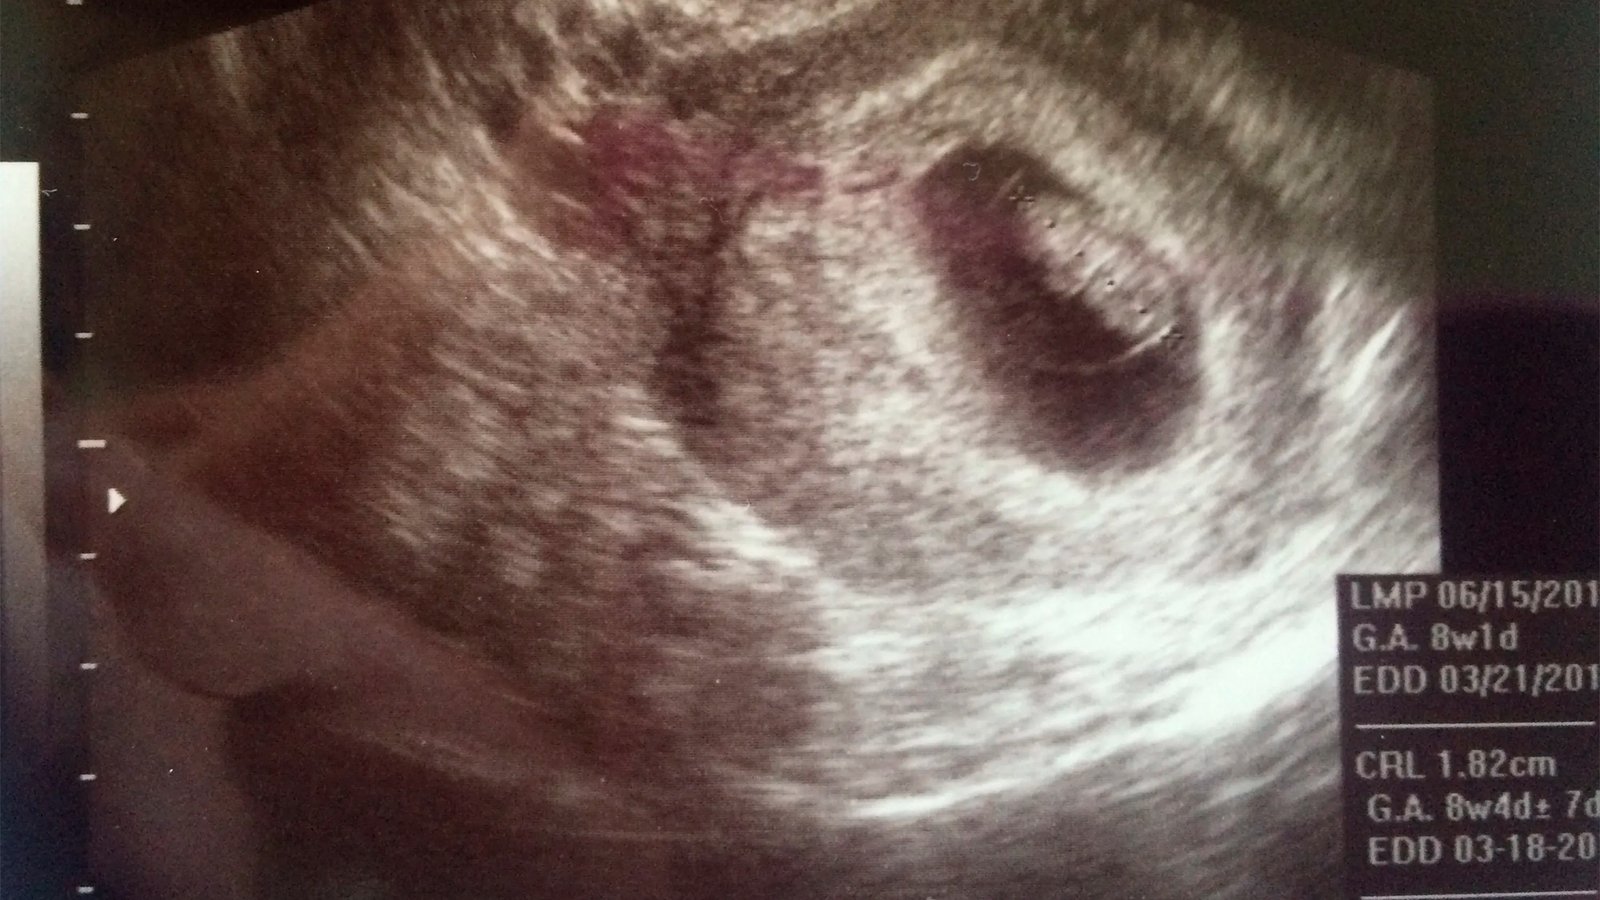

Gerar – 2º mês

Série Gerar – 2º mês